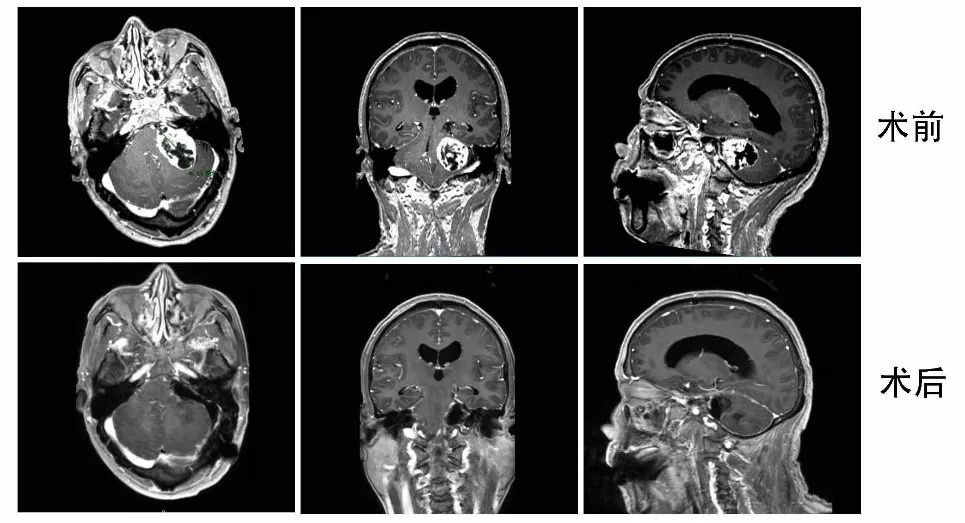

患者陈先生因左侧听力下降5年,伴间断头晕2年来诊。门诊行颅脑CT提示左侧桥小脑角区占位,于神经外五科住院治疗。入院后行颅脑MRI检查提示左侧桥小脑角区巨大占位,最大直径为4.6cm,同侧内听道扩大,四脑室及小脑脑干受压移位明显,幕上出现脑积水趋势,考虑巨大听神经瘤。

神经外五科主任王喆团队进行仔细术前讨论,结合患者病史及影像学检查,考虑左侧巨大听神经瘤,肿瘤体积大且已压迫周围脑干、小脑及四脑室,幕上脑室有扩张趋势,手术指征明确,如不积极手术治疗,将会导致急性梗阻性脑积水危及生命。患者入院完善术前检查后,在神经电生理监测下顺利完成手术,术中面神经完整保留,肿瘤切除满意,术后患者恢复良好,面神经功能保留完好,已顺利出院。